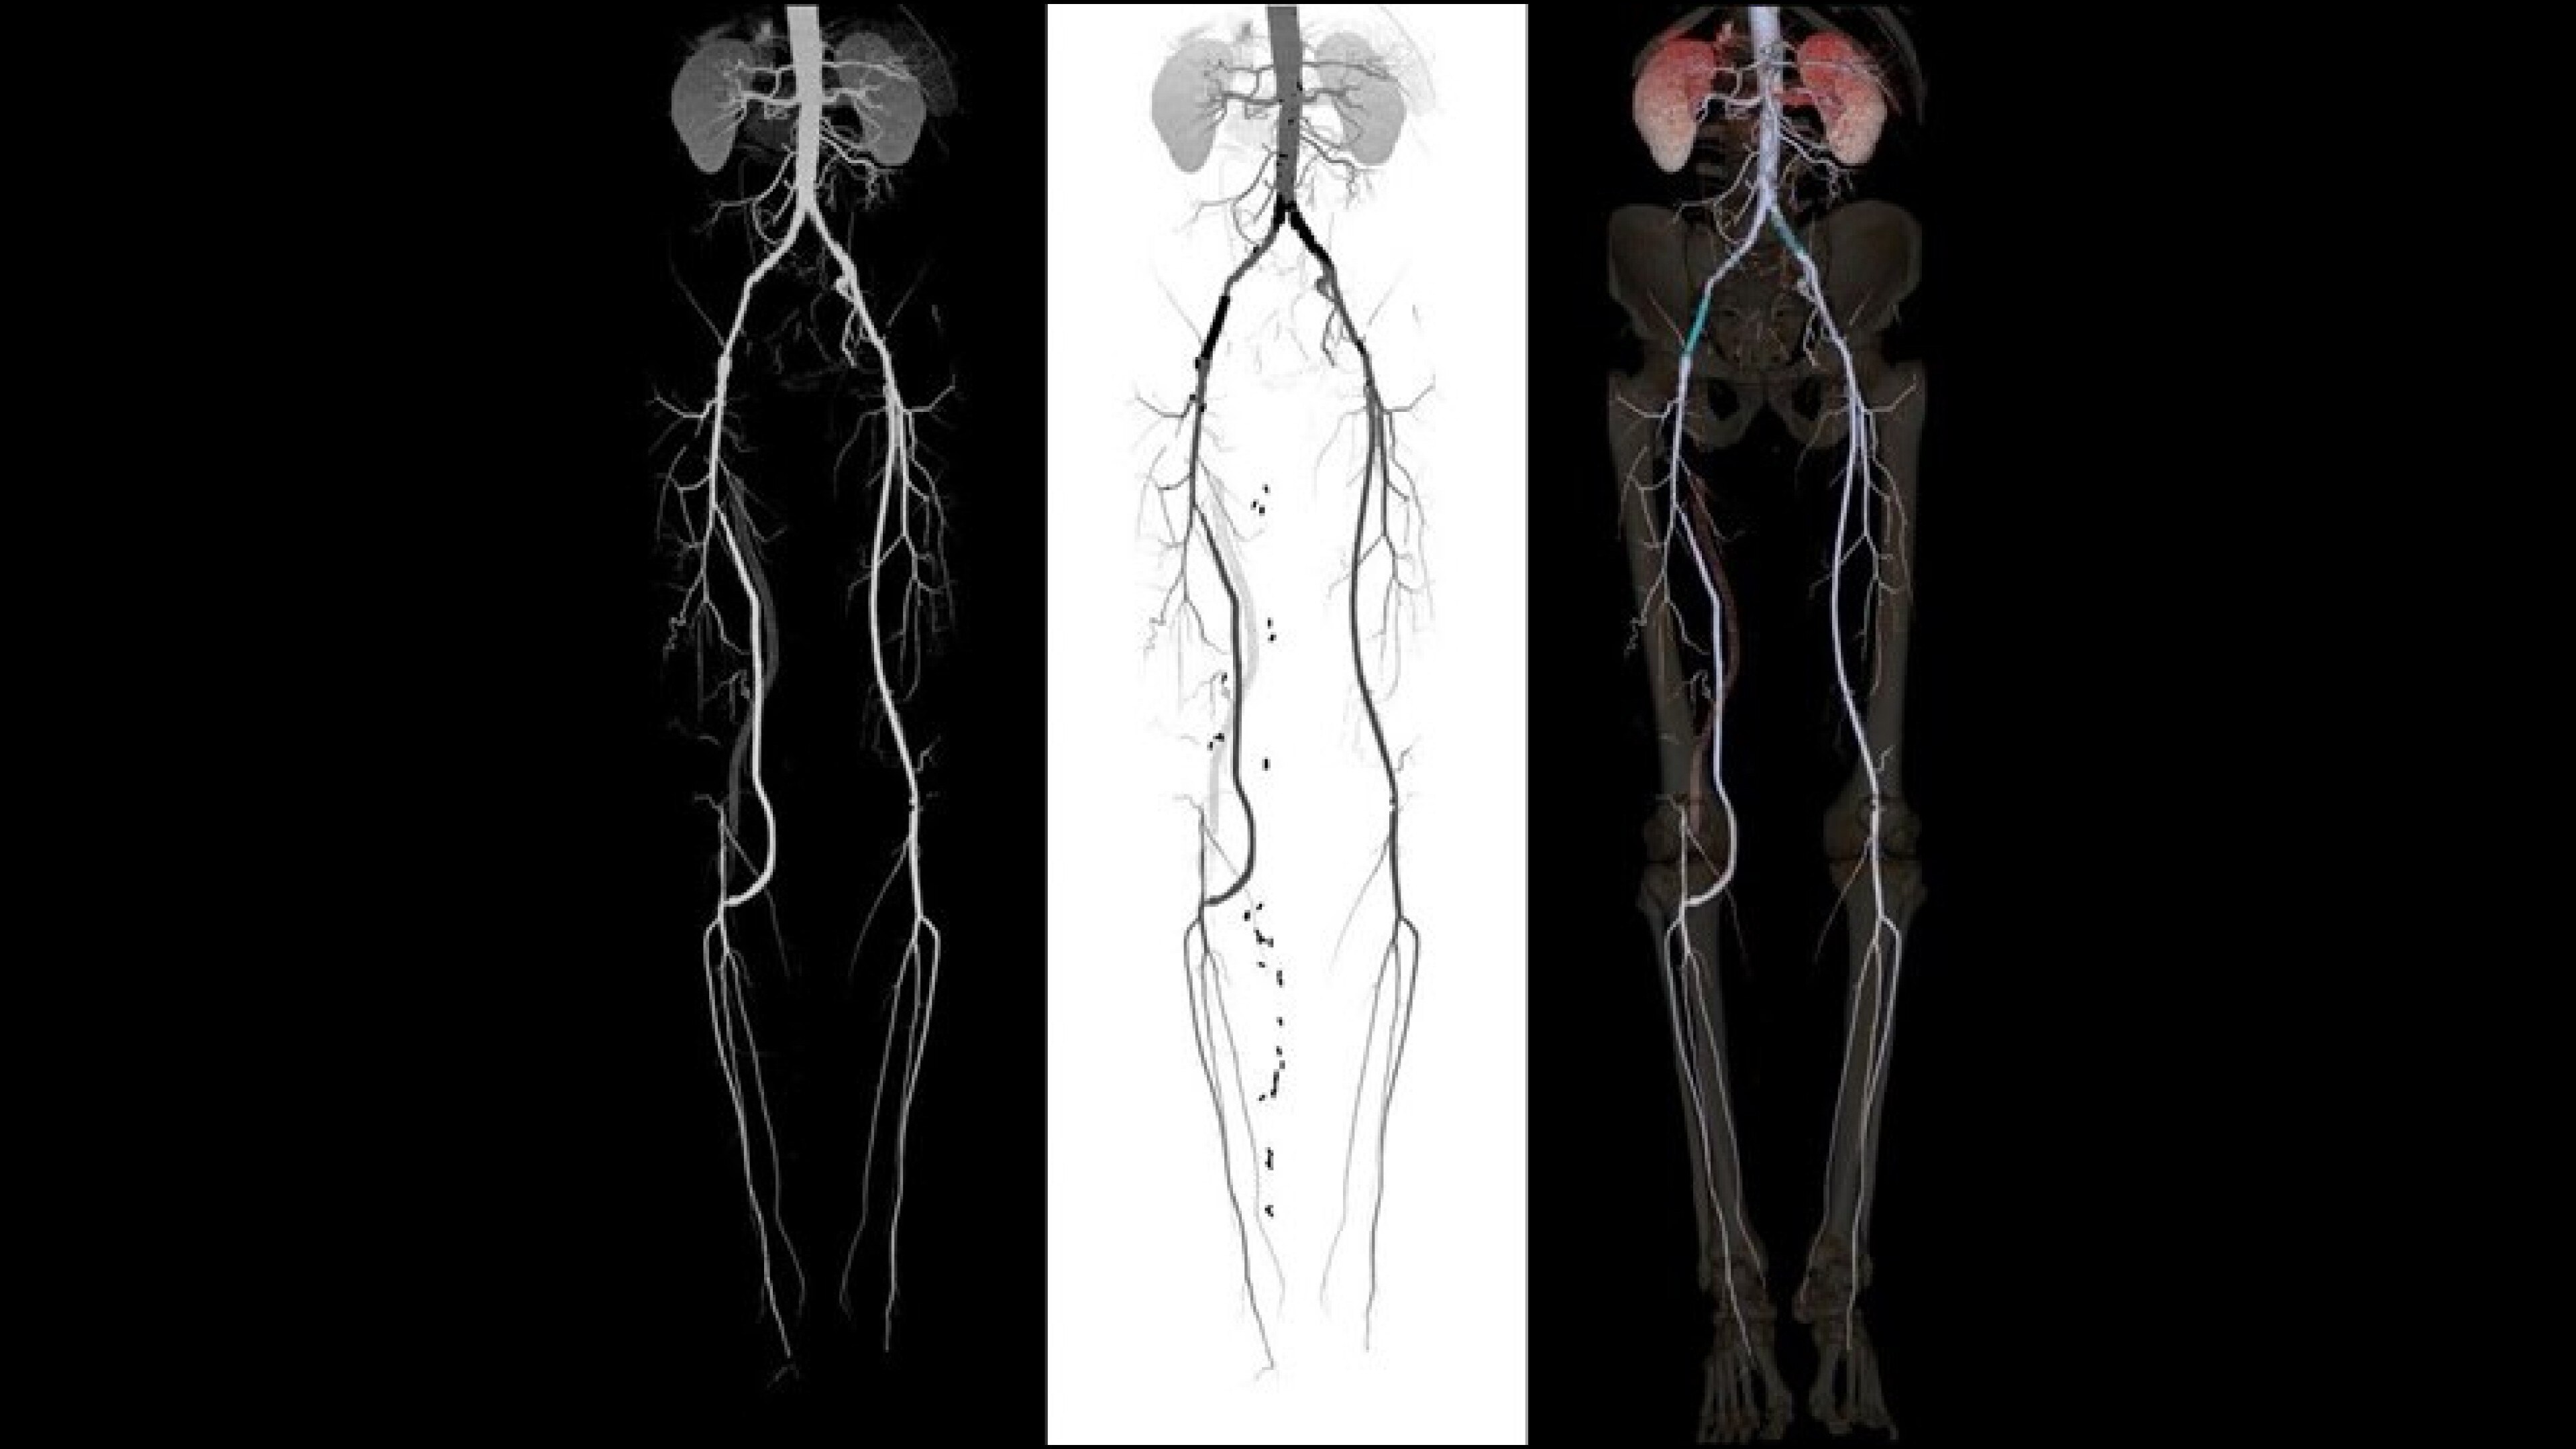

Autobone & VesselIQ Xpress

Fast and efficient vessel analysis from CT Angiography exams.

Automated detection of aorta and illiacs with auto-labeling of vessels

• Automated detection of aorta an illiacs with auto labeling of vessels.

• Thrombus detection with measurements and comparison over time.